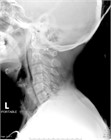

1. 食道破裂(esophageal rupture)、食道穿孔(esophageal perforation)や食道断裂(esophageal disruption)とは、食道壁に全層性に断裂(disruption)や損傷(trauma、injury)が生じた状態である。

1. 胸痛、呼吸困難、ショックなどの症状を呈する。